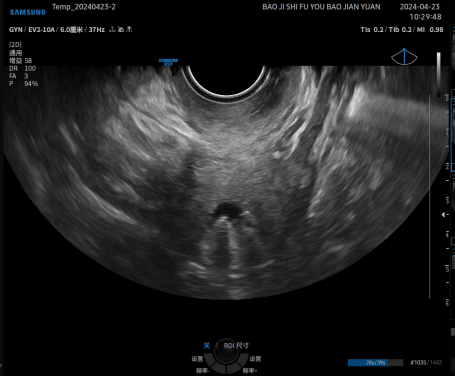

病例再现 / 03

二维超声不能确定是否存在的内膜息肉,宫腔水造影则清晰可见,还能精准定量定位息肉的大小及位置。